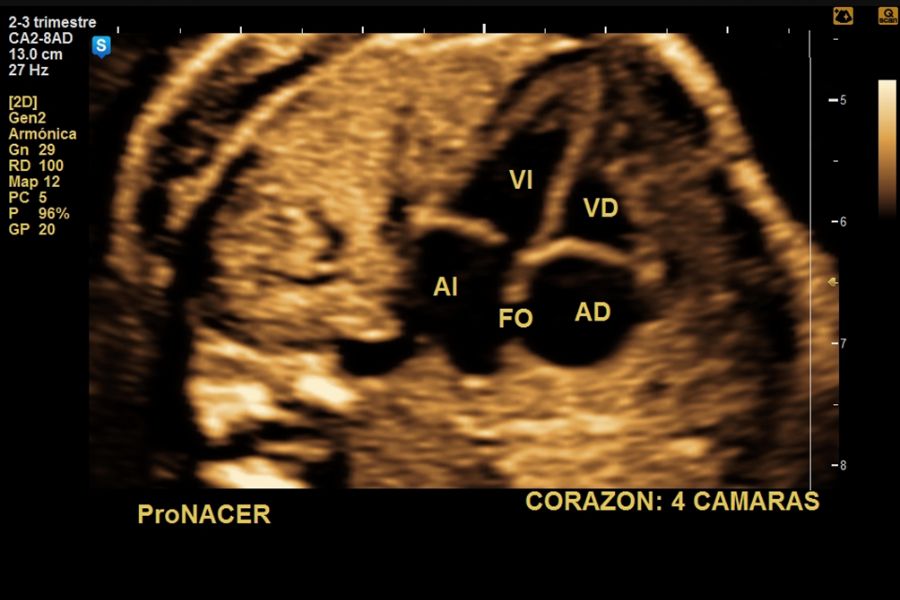

Se controlan más estrechamente a las gestaciones MONOCORIALES (con una sola placenta). Las gestaciones con gemelos monocoriales son embarazos de mayor riesgo debido al mayor riesgo de complicaciones que pueden tener con respecto a las gestaciones bicoriales (dos placentas).